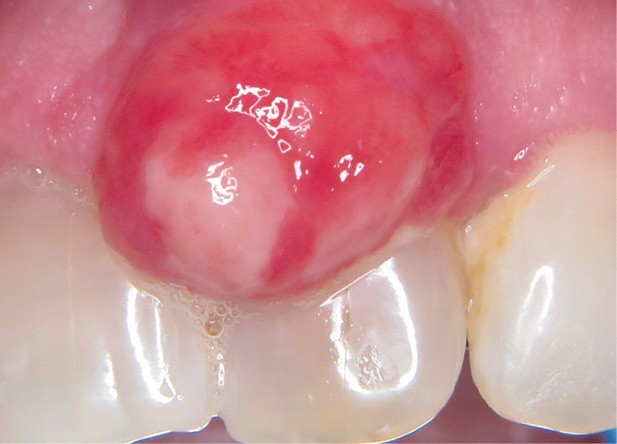

1. Épulis inflammatoire (plasmocytaire)

- Forme gravidique fréquente au 2e et 3e trimestres (fig. 1b). Favorisée par l’augmentation du taux de progestérone, œstrogènes, prostaglandines entraînant une vasodilatation.